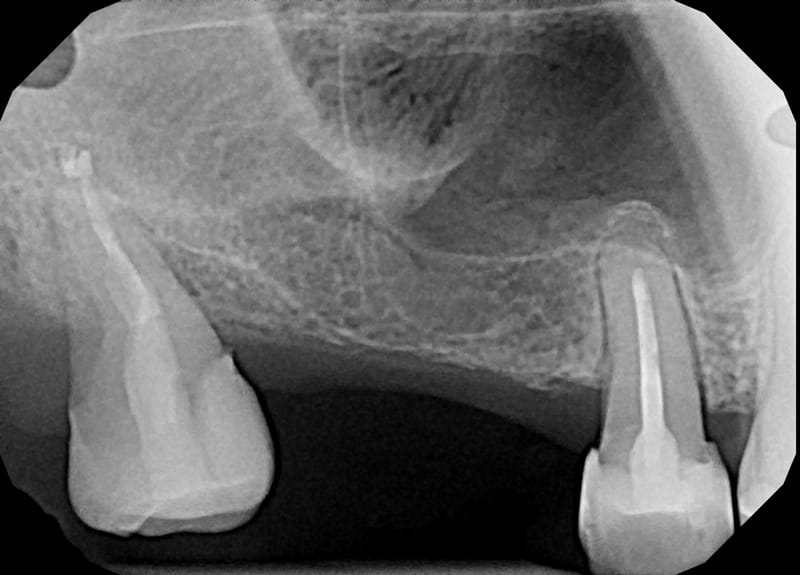

Leczenie pierwotne bezinstrumentacyjne d.18

Leczenie pierwotne d.18